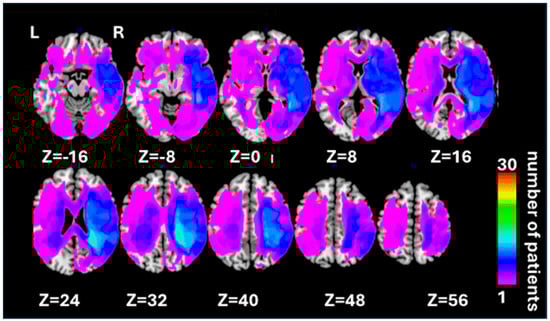

| Factor | Size (Voxels) | Z-Score | Coordinates (X, Y, Z) | Brain Structure |

|---|---|---|---|---|

| Automatic self-reference | ||||

| 1384 | 3.44 | 34 26 −42 | Right ITG 1 | |

| 50 | 3.41 | −10 50 4 | Left vmPFC 2 | |

| Control processing | ||||

| 405 | 3.93 | 44 −46 62 | Right IPL 3 | |

| 275 | 3.74 | −28 −66 52 | Left IPL 3 | |

| 343 | 3.39 | −46 −10 4 | Left AIC 4 | |